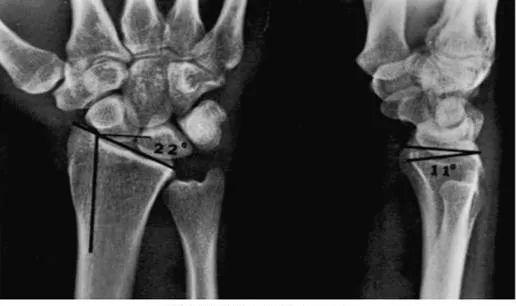

桡骨远端关节面呈由背侧向掌侧、由桡侧向尺侧的凹面,分别形成掌倾角(10°~15°)和尺倾角(20°~25°)。

掌侧倾斜角:桡骨远端与腕骨形成关节面,其背侧边缘长于掌侧,关节面向掌侧倾斜为10~15°。

尺侧倾斜角:桡骨下端外侧的茎突,较内侧长1.5cm,故其关节面向尺侧倾斜20~25°。